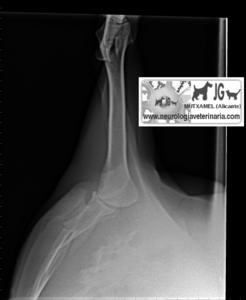

Radiografía del mismo paciente en el momento del accidente (nótese el neumotórax consecuente a la fractura de escápula) |

Nótese la perforación de la caja torácica |